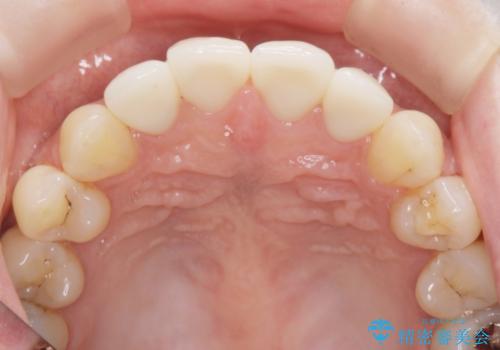

自然な歯の仕上がりに満足いただくことができました。